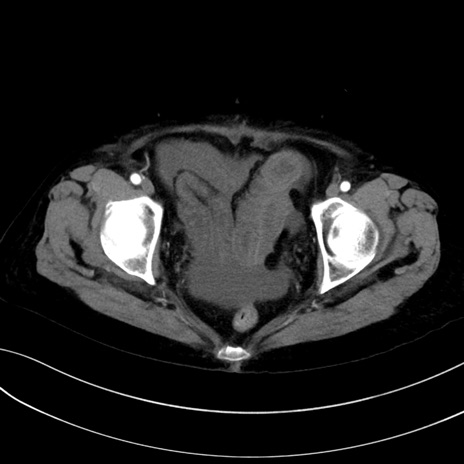

症例13 CT(横断像)1日半後